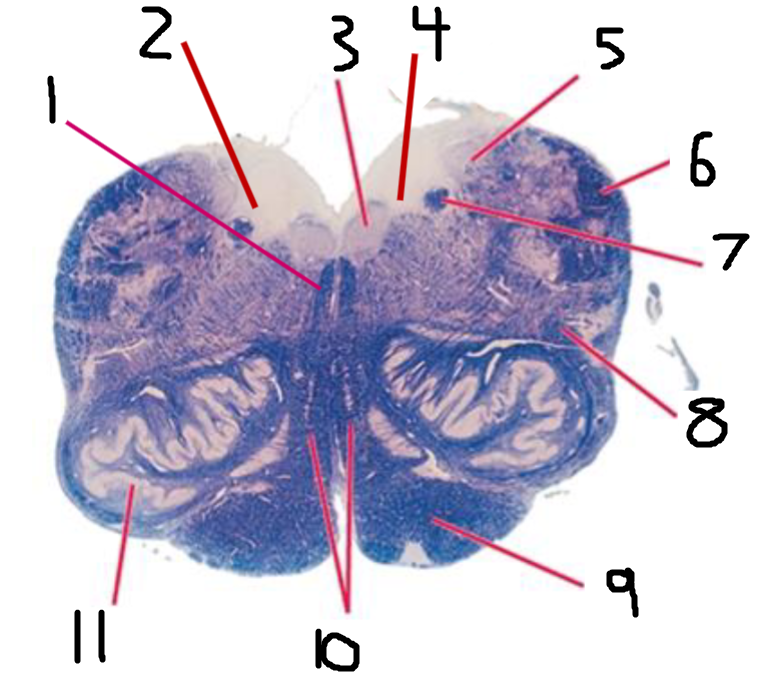

#1 is the:

Fornix

#2 is the:

Thalamus

#3 is the:

Caudate

#4 is the:

Middle Cerebellar Peduncle

#5 is the:

Inferior Olivary Nucleus

#6 is the:

Corticospinal Tract

#7 is the:

Hippocampus

#8 and #11 is the:

Lateral Ventricle

#9 is the:

Internal Capsule

#10 is the:

#12 is the:

Corpus Callosum